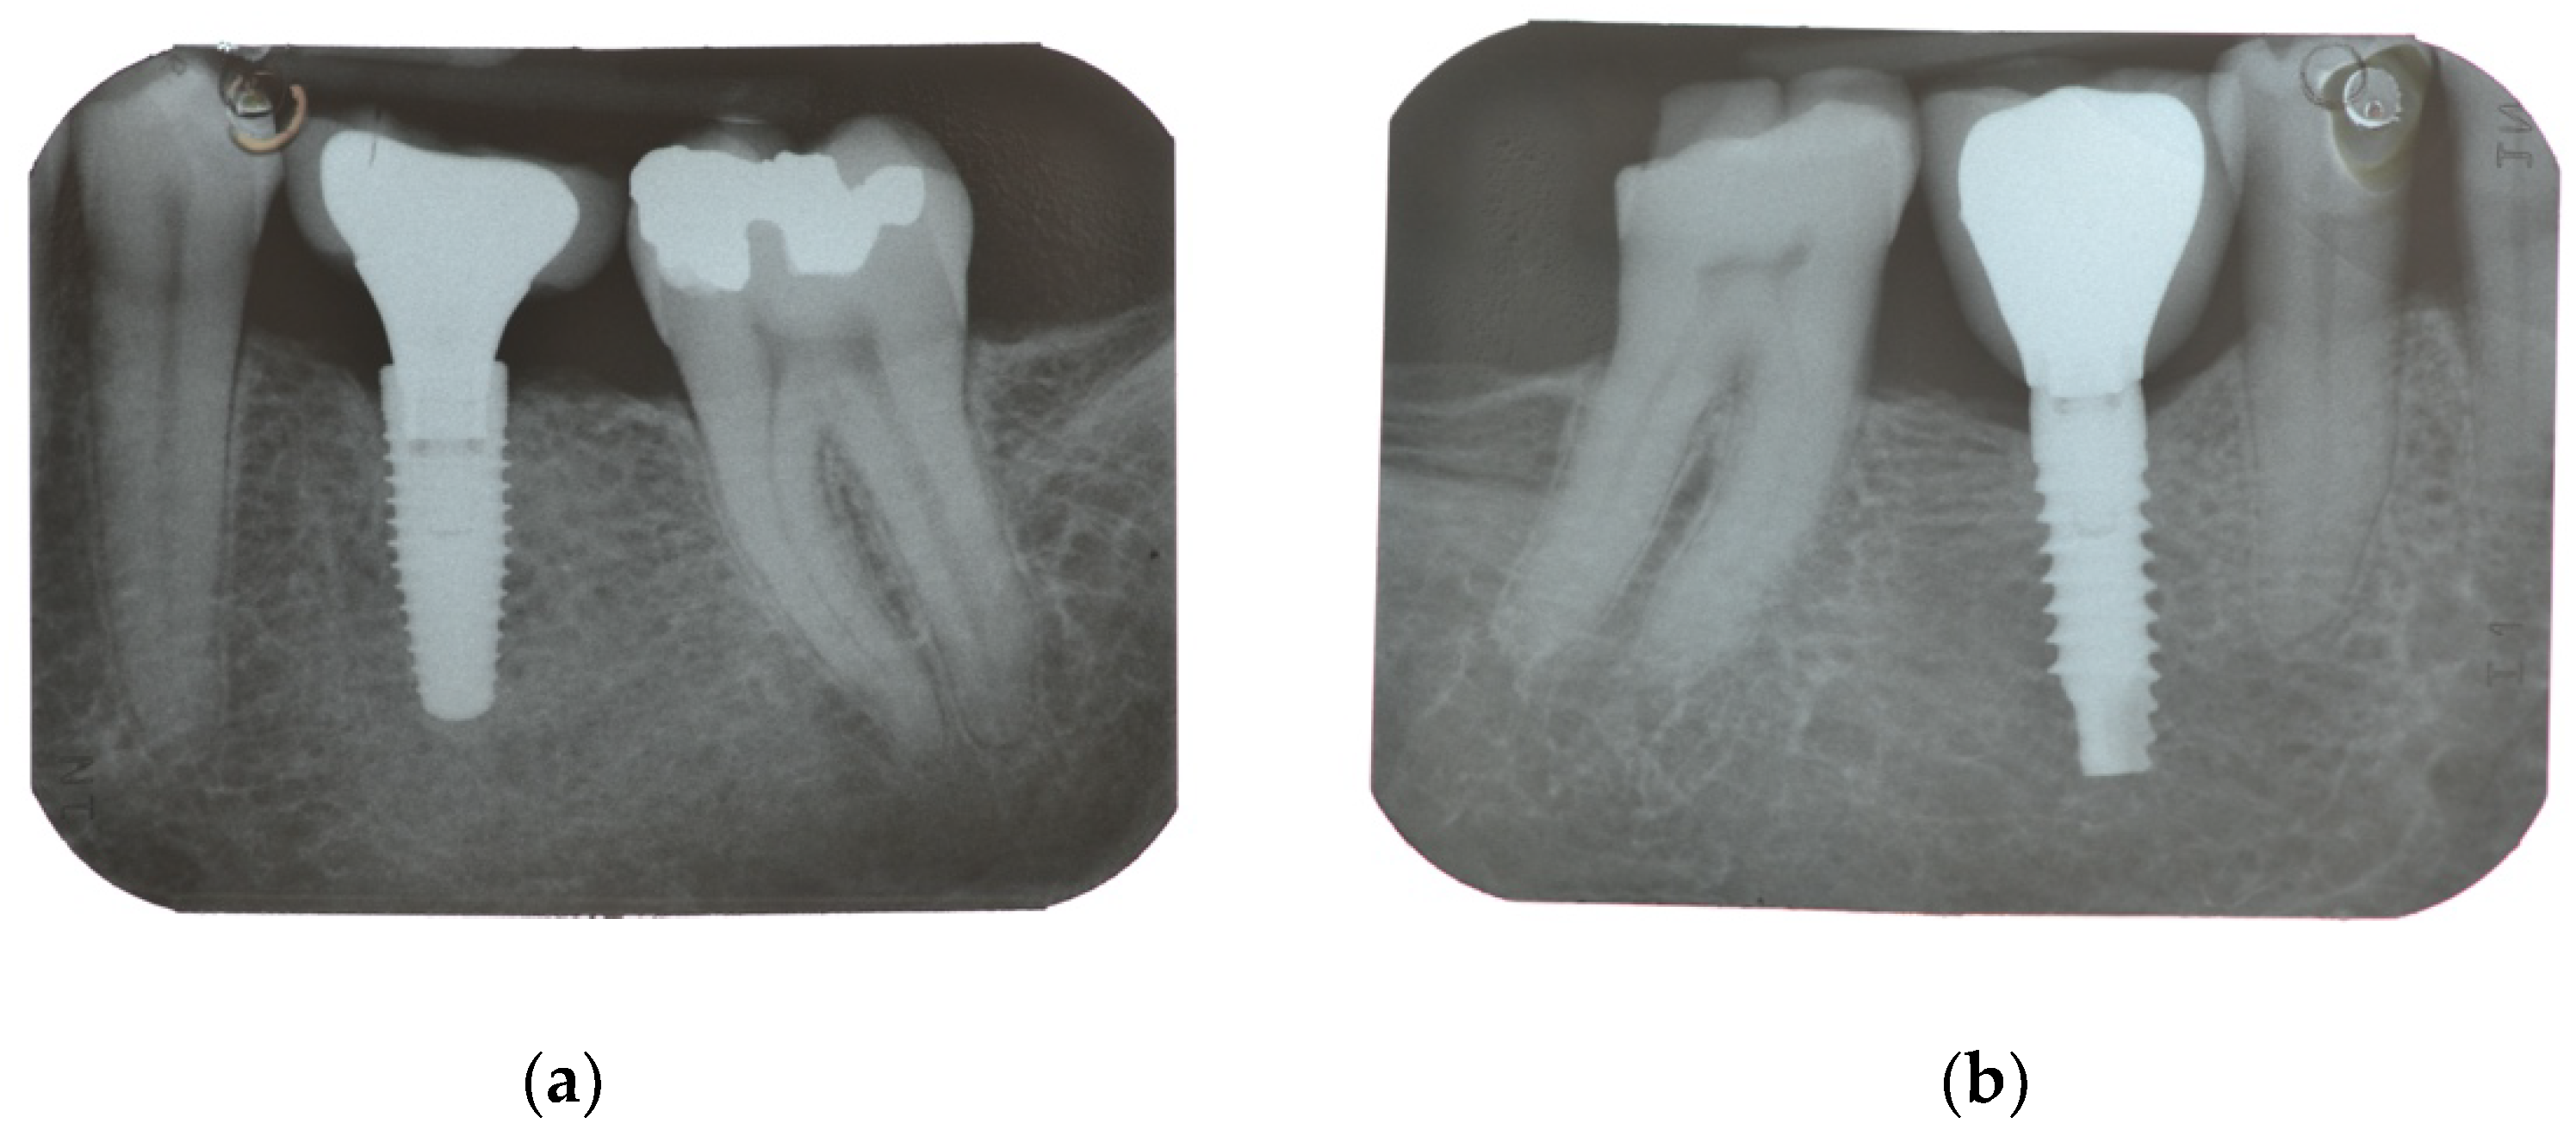

| Secondary Outcome | Marginal bone loss (MBL) | Marginal bone level changes were assessed using intraoral digital periapical radiographs at implant placement (baseline), and at after one year on function. Intraoral radiographs were taken with the parallel technique with customized holder. All the radiographs were evaluated under routine conditions. The software has been calibrated for every single image using the known distance of the implant diameter or length. The distance from the reference point at the implant neck to the first bone to implant contact were taken as the horizontal marginal bone level at both mesial and distal aspects. The average radiographic values of mesial and distal measurements were taken for each implant. Variation of the marginal bone levels at different time was taken as marginal bone loss. |

| Implant placement | 0.04 ± 0.06 (0.00 to 0.07); n = 15 | 0.01 ± 0.02 (0.00 to 0.02); n = 15 | 0.128 |

| One-year follow-up | 0.99 ± 0.71 (0.61 to 1.36); n = 14 | 0.65 ± 0.48 (0.40 to 0.91); n = 13 | 0.166 |

| Difference | 0.96 ± 0.72 (0.58 to 1.34) | 0.65 ± 0.48 (0.40 to 0.90) | 0.192 |